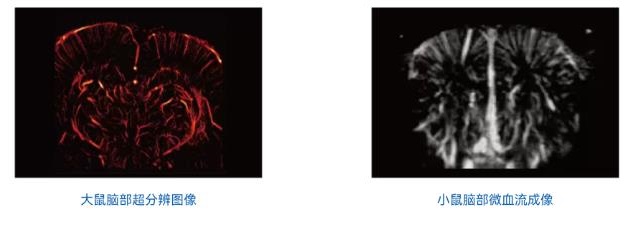

超分辨率超声成像

肿瘤微血管成像:异常微血管生长是癌症的特征之一,超分辨率超声成像可用于癌症的基础研究和临床管理,如早期检测、诊断和治疗反应评估。在肿瘤体积尚小时,通过微血管形态变化实现早期诊断

脑微血管成像:提供大脑范围的成像覆盖和微米级的空间分辨率,同时测量单个血管的血流速度,例如在脑卒中研究中早期检测缺血半暗带微血管血流变化,指导溶栓治疗。在阿尔茨海默病模型中观察淀粉样斑块区血管损伤,研究疾病机制

成像效果展示